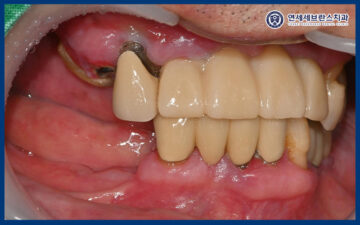

25.06.21 / 25.07.19

이렇게 임플란트의 치유기간을 거쳐

잇몸뼈와 잘 결합되어

최종 보철 작업을 시작하였습니다.

25.07.19

그리고 맞춤형 지대주에 맞는

최종 보철을 제작하여

맞춰보았습니다.

보철물의 형태와 색상,

교합 상태를 꼼꼼하게 확인한 뒤

불편한 부분은 없는지 점검하며

세밀한 조정을 시행하였습니다.